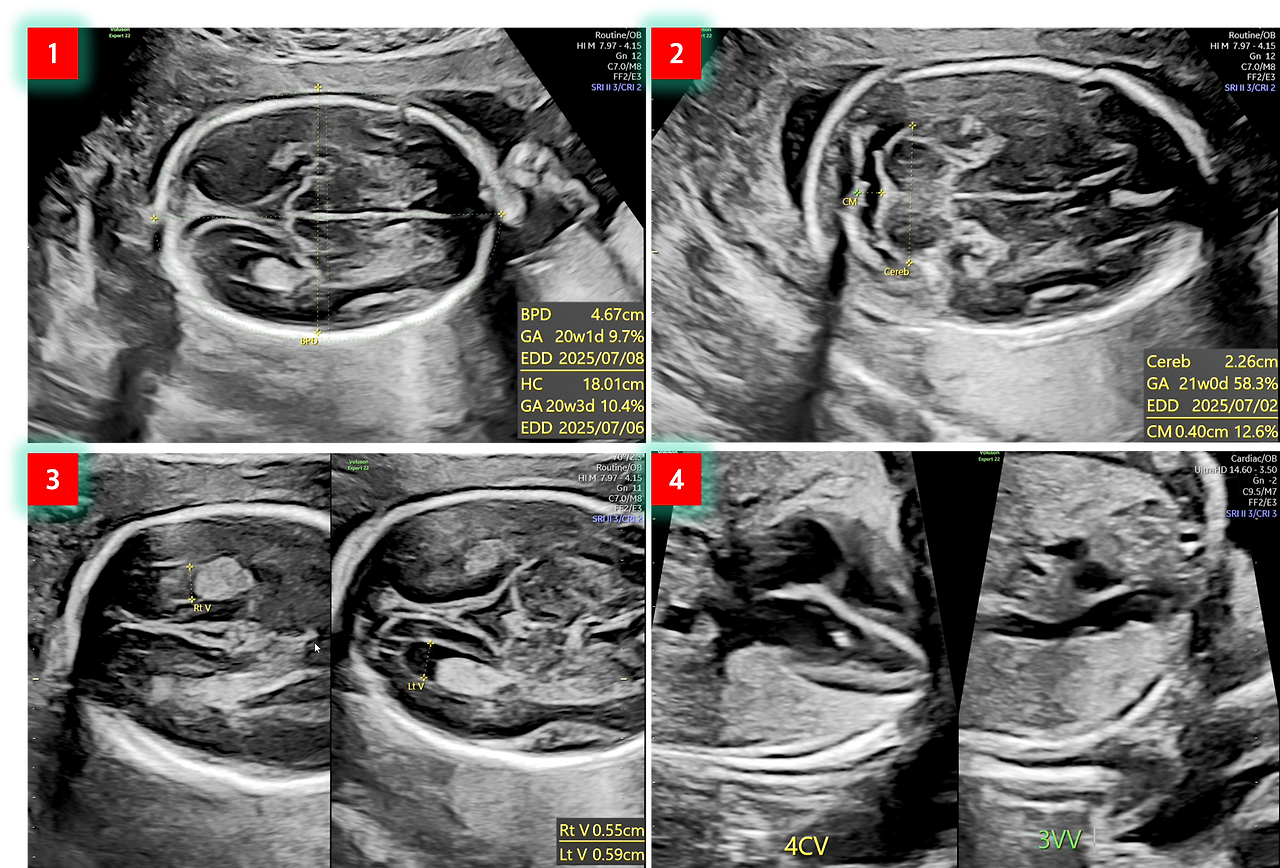

1번 사진을 보면 BPD(Biparietal Diameter, 태아 머리 직경)는 20주 1일이고, HC(Head Circumference, 태아 머리 둘레)는 20주 3일로 표시가 되네요. 현재 딸 애가 임신 21주이니까 며칠 정도 차이가 있지만 정상적으로 크고 있다고 보이네요. 참고로 GA(Gestatioal Age)는 임신 주수이고, EDD(Expected Data of Delivery) 출산예정일입니다.

2번 사진에서 Cereb(Cerebellum)은 소뇌를 말하고요. 그리고 CM(Cisterna Magna)은 '소뇌수뇌수조'라고 하네요. 발음하기도 어렵고 무슨 말인지 도통 어려워서 찾아보니, 소뇌아래에서 뇌척수액이 흐르는 공간이라고 합니다. 잘 모르겠지만 소뇌수뇌수조의 크기를 측정하면 태아의 뇌실 확장증, 뇌수종, 뇌량 무형성증 등의 뇌 기형을 확인할 수 있다고 하네요. 아무런 말도 없었다면 이것도 정상이라는 것이겠지요.

3번 사진은 심장의 우심실(RV: Right Ventrice)과 좌심실(LV: Light Ventrice)을 말하는데, 좌심실은 타원형으로 심장에서 가장 크고 튼튼하다고 합니다. 아마 여기서는 형상을 육안으로 보고 이상 여부를 확인하는 것 같습니다.

4번 사진의 4CV(Four Chamber View)는 태아 심장을 4방향으로 관찰한 단면상으로 '4방 단면상'이라고 합니다. 여기서는 두 개의 심방과 심실의 구성, 크기의 비교, 올바른 위치 확인 등과 같은 형태학적인 것을 파악하는 것 같습니다. 3VV(Three Vessel View)는 '3 혈관상'이라고 하며, 태아 심장 기형의 진단에 많은 정보를 제공할 수 있어 매우 중요한 항목이라고 하네요. 여기서는 혈관의 수/순서/크기 그리고 혈관의 배열 위치 등을 확인할 수 있다고 합니다.